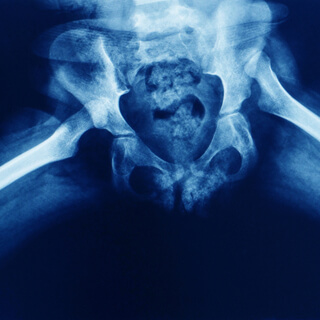

يعد خلع الولادة أو خلع التنسج النمائي المعروف ب (DDH) عبارة عن تطور غير طبيعي لمفصل الورك بحيث تكون الكرة الموجودة في الجزء العلوي من عظم الفخذ غير مستقرة داخل تجويف الورك، وقد تكون أربطة المفصل مشدودوة أو مرتخية.

يمكن أن يكون خلع الولادة موجودًا في كلا الوركين أو في أحدهما فقط، وينتشر غالبًا في الفتيات والأولاد البكر، أمّا أبرز أسباب إصابة الطفل به فهي: